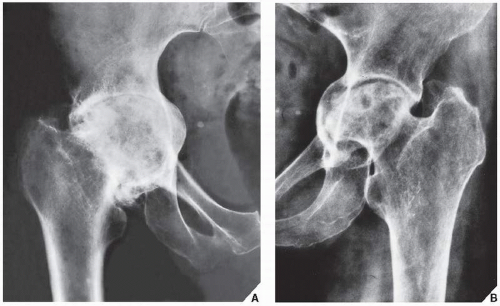

Рентгеновские снимки: Синовит тазобедренного сустава